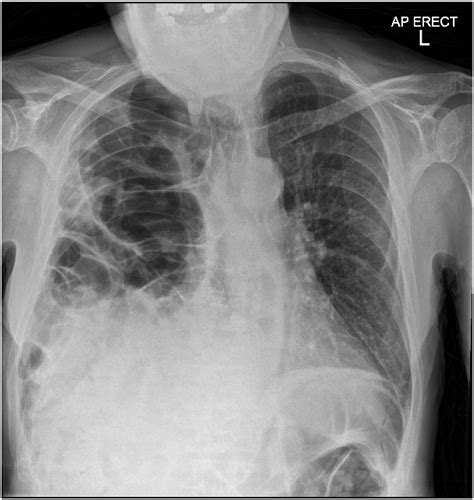

Chest X-ray: Provides a basic view of the chest and can show the presence of a hernia.

CT Scan: Offers detailed images of the chest and abdomen, helping to identify the location and size of the hernia.